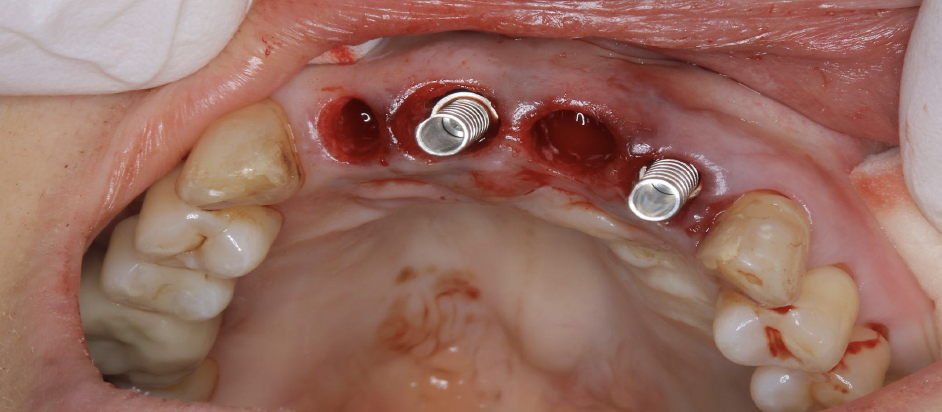

当日、抜歯とインプラントを同時に入れました。

4本抜歯して2本のインプラントを入れました。

手術直後、1週間後の抜糸時、3か月後の写真です。